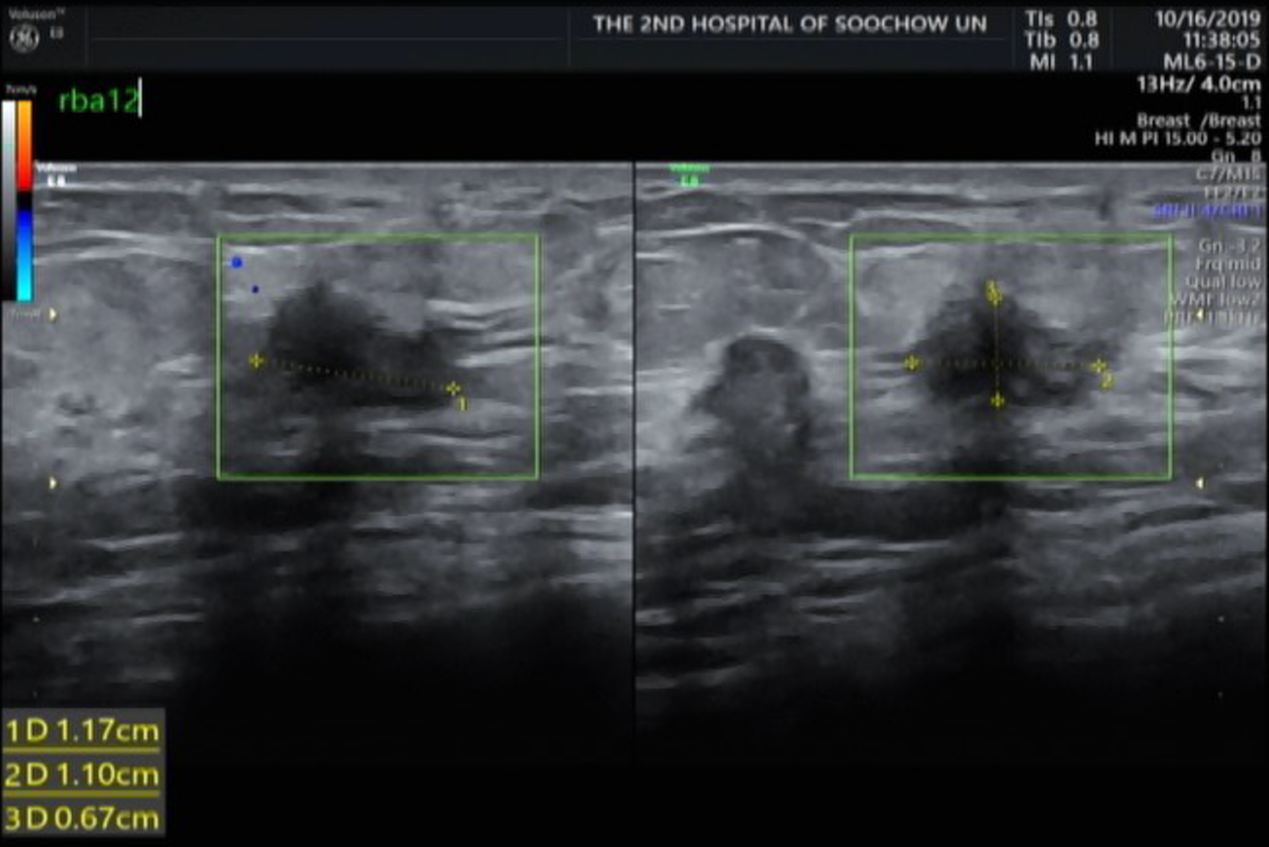

现病史:患者于2019 年 10 月无意间发现右乳存在肿块,于医院就诊。查乳腺彩超(2019-10)示:右乳低回声(BI-RADS 4B 类)、右腋下多发异常淋巴结;穿刺病理示(右乳)浸润性导管癌,免疫组化 ER(-)、PR(-)、HER-2(3+)、Ki-67(+,约 60%);胸部 CT (2019-10)示:两肺多发转移,排除颅内及骨转移。PS :1 分。

2019 年 10 月乳腺及腋窝淋巴结彩超:右乳 1×1cm 肿块,乳腺彩超提示右乳低回声(BI-RADS 4B 类)、右腋下多发异常淋巴结;穿刺病理示(右乳)浸润性导管癌,免疫组化 ER(-)、PR(-)、HER-2(3+)、Ki-67(+,约 60%);

图1 乳腺及腋窝淋巴结彩超